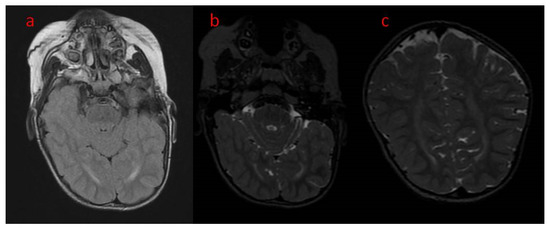

| 16 The present study | Areas of incomplete myelination (in the area of the triangles of the lateral ventricles and around the occipital horns) | Cortical visual impairment, poor eye contact, with movement disorder | Hypotonia, joint contractures | Severe global developmental delay | Dysphagia (only liquid food) | Difficult to treat, ASM resistance (valproic acid, topiramate, vigabatrin, phenobarbital, levetiracetam, phenytoin, clobazam, clonazepam, nitrazepam, lamotrigine, carbamazepine, and zonisamide), steroid therapy (adrenocorticotropic hormone, methylprednisolone—break), vagal nerve stimulation, ketogenic diet intolerance (due to reluctance to drink) |